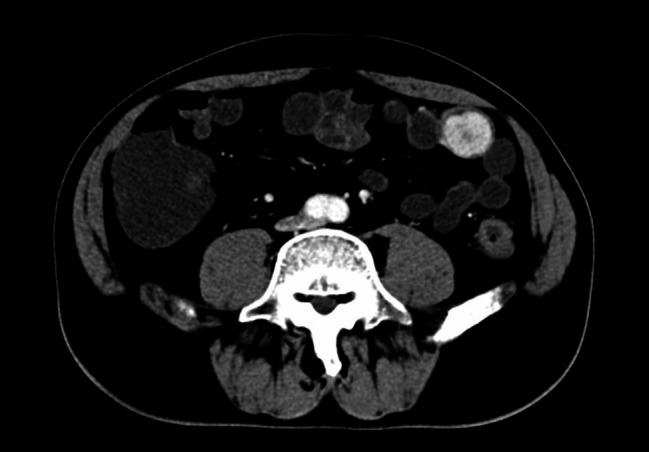

Gastrointestinal stromal tumors (GISTs) are the most common mesenchymal tumors of the gastrointestinal tract. The most common mutations in GISTs are those in receptor tyrosine kinase (KIT) and platelet-derived growth factor receptor alpha (PDGFRA). GISTs without KIT or PDGFRA mutations are defined as wild-type (WT) GISTs. The molecular changes, prognosis, and treatments of WT GISTs remain uncertain. Among WT GISTs, neurotrophic tyrosine receptor kinase (NTRK) fusions have rarely been reported. We report a case of quadruple wild-type GIST harboring a novel CDC42BPB::NTRK3 fusion. In this study, we described a 66-year-old male patient with intrajejunal lesion. This case showed massive lymphocytic and plasma cell infiltration, which caused diagnostic difficulties in morphology. CDC42BPB::NTRK3 fusion was detected via next-generation sequencing (NGS), and this finding was confirmed by fluorescence in situ hybridization (FISH), which revealed NTRK3 breakage. However, the expression of the Trk protein in tumor tissue was not detected by immunohistochemistry (IHC). This finding expands the genetic spectrum of NTRK rearrangements in GISTs.